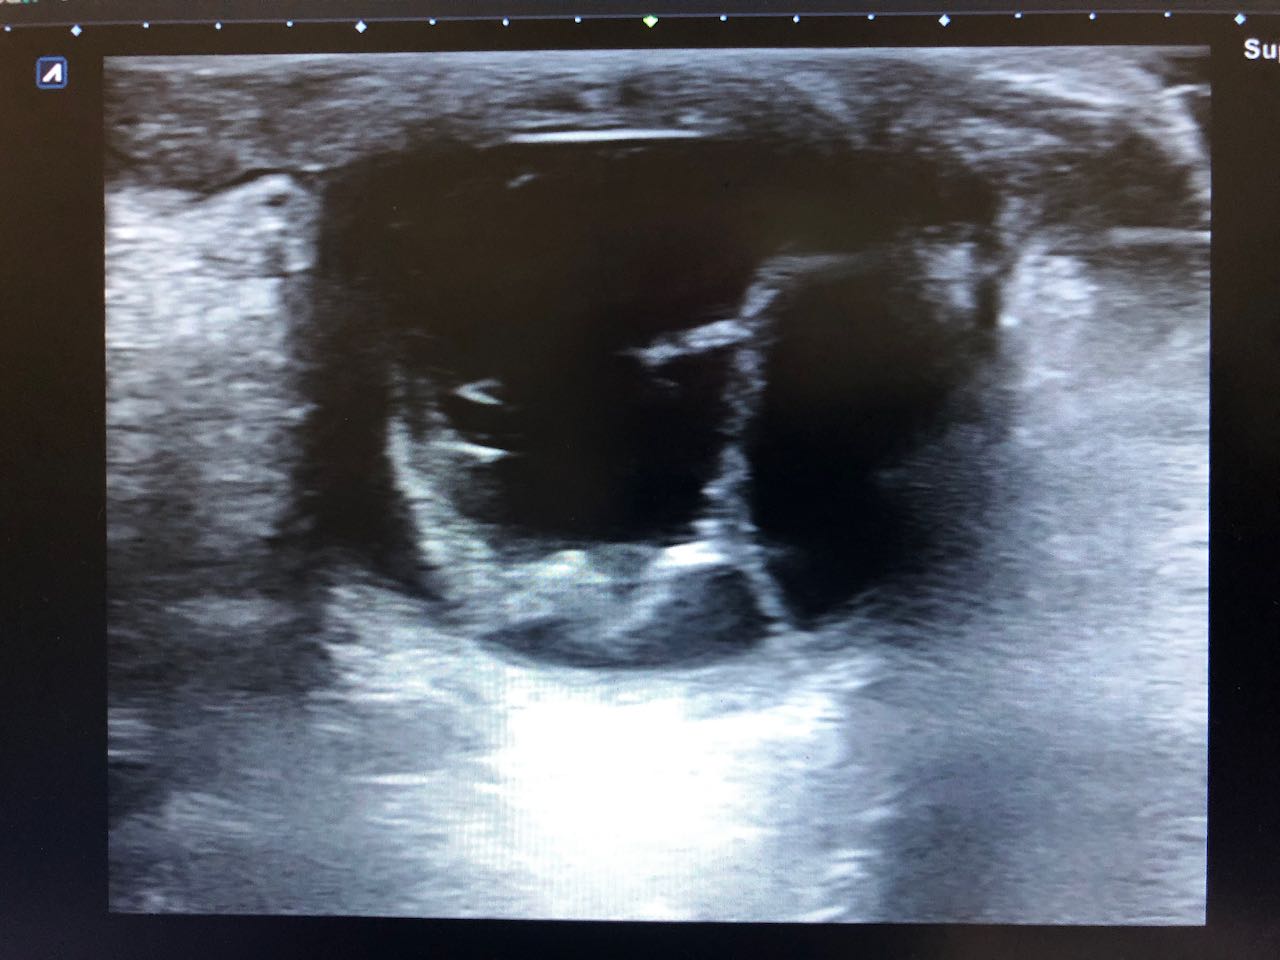

Citado en cita forzada, refiere molestias oculares, con sensibilidad a la luz, que le obliga a mantener el ojo cerrado, acude por precisar gotas para la conjuntivitis, ante la dificultad idiomática y considerar que el paciente es poco preciso en la descripción de los síntomas, pues ante la pregunta de «si tiene dificultades en la visión» el paciente se reitera que le molesta muy cierra el ojo, y en relación con el dolor que es como si tuviera algo que le roza. Se procede a la exploración ocular, observando un ojo derecho normal con blefaroespasmo en ojo izquierdo (OI), hiperemia ocular tarsal, con pupilas reactivas, fluortest negativo y presión intra ocular (medición palpebral), normal en los dos ojos. Ante la incongruencia de la sintomatología referida y los hallazgos exploratorios, se considera indicado hacer una ecografía ocular, en la que se apreció signos de desprendimiento de retina y coroides del OI.

Se confirma desde Oftalmología el diagnóstico: Desprendimiento de retina casi completo junto a desprendimiento de Coroides temporal en OI de contenido hiperecogénico, no se aprecian masas.